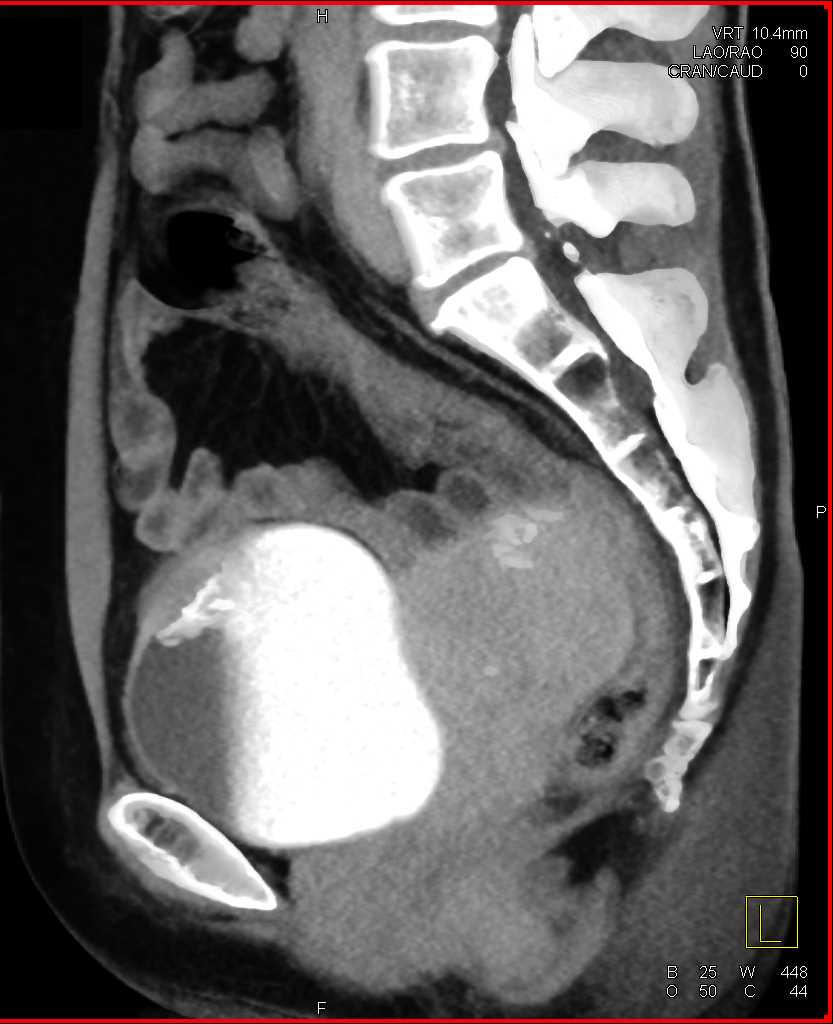

Urachal Carcinoma of the Bladder